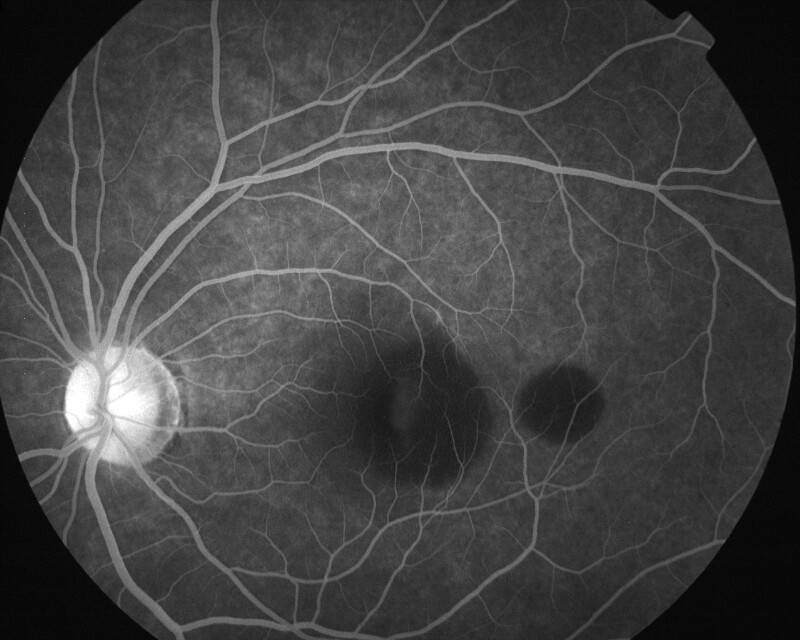

IMG0018.jpg